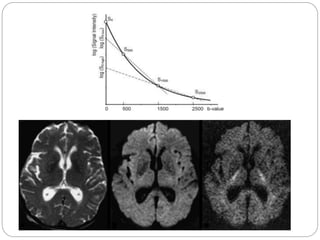

ADC: Apparent Diffusion Coefficient

 ADC is measure of diffusion

 Calculated mathematically from b-value=0 and

higher b-value images

 Signal attenuation of a tissue with increasing

value plotted on graph with relative signal

intensity on y-axis and b-value of x-axis

 Resultant slope of line is ADC

 Done on pixel by pixel basis by computer

 To user it is available as ADC map

 ADC is independent of ‘B’

 Reduced ADC is ‘restricted diffusion’ [bright area]

on DWI

 While on same area will be dark on ADC map

 ADC value from map for AOI measured in

ADC plot

T2 Shine Through

 Signal intensity on DWI (higher b-value images) not

only depends on ADC but also on T2 relaxation time

of tissue

 High T2 tissue appears bright on DWI (even not

restricted)

 ADC map helps to differentiate T2 shine through

from actual

 Or T2 shine through are exponential images formed

by ratio of DWI images divided by T2-w (b=0)

images in same series

 These images are called eADC by some vendors

(Philips)

 Truly restricted area is bright on eADCeADC